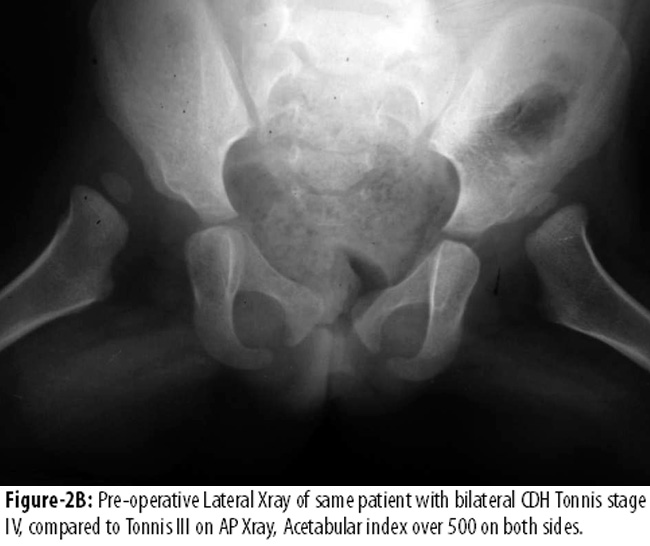

Figure-2AB shows Tonnis level III11 dislocated hips on both sides, with an acetabular index over 50° in an 18 months aged patient.

Figure-2C appreciates excellent contained hips, acetabular index 17° and a well developed hip at 30 months follow-up.